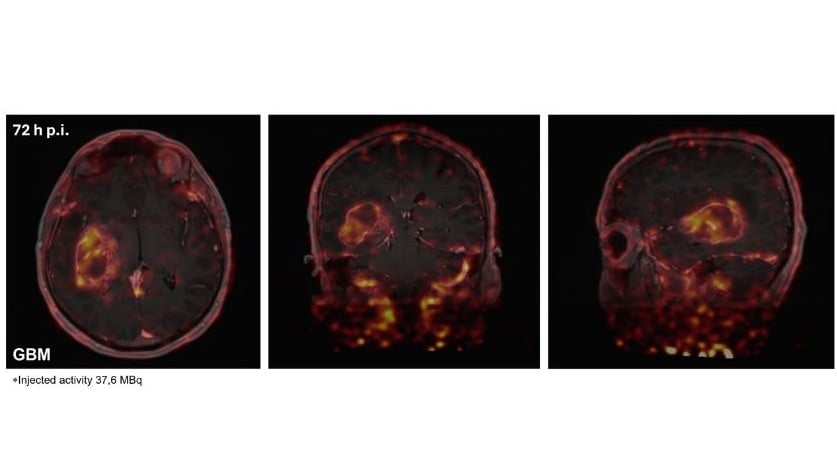

Positron emission tomography (PET), using radiolabelled mAbs, antibody fragments or engineered protein scaffolds (immuno-PET), has the potential to acquire information non-invasively and can be highly complementary to analyses based on tissue acquisition. Accordingly, immuno-PET agents might accurately identify the presence and accessibility of the target and provide a rapid assessment of tumour response to a variety of treatments in a timely fashion (e.g. within 1-2 weeks of treatment initiation).

Furthermore, immuno-PET agents can provide information about the heterogeneity of both target expression and therapeutic response, which are increasingly recognised as key factors in treatment resistance. This especially relates to patients with advanced disease in whom target expression may vary from site to site and a biopsy of a single local or metastatic deposit may not accurately reflect the situation across the entire disease burden. Although introduction of immuno-PET into routine clinical practice may add complexity and increase costs, with appropriate use this imaging modality has the potential to identify patients likely to benefit from therapy and assess the efficacy of novel target-specific drugs.

Against this background, our research focuses on the development and characterisation of targeted-PET radiotracers, including protein-based theranostic agents that enable smart monitoring of immunotherapies and expand opportunities for personalised medicine approaches.